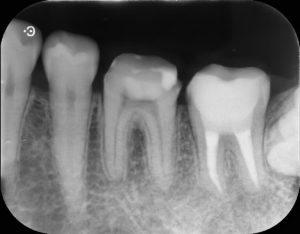

治療前

左下第二大臼歯部に不良補綴物をみとめたため、レントゲン検査を行うと根尖部透過像がみられた。根管内に破折器具がみられたため、破折器具の除去および根管内の感染除去を行った。経過観察後、根尖部透過像の縮小をみとめたため、歯冠修復を行った。